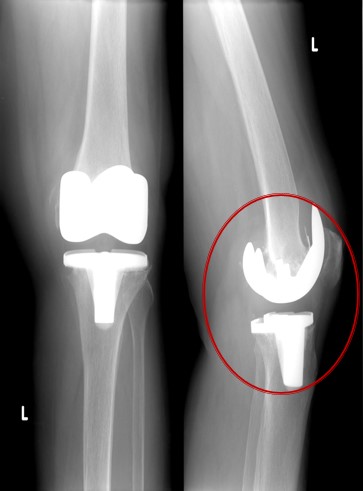

Приклад 3. Хвора К. 52 років. Діагноз: Деформівний IVст. гонартроз, стан після ТЕП лівого КС (2013р.). ІМТ хворої складає 35 балів. Асептична нестабільність компонентів ендопротеза лівого колінного суглоба, міграція великогомілкового компоненту (2017 р.) (рис. 2 а). Хворій виконано ревізійне ендопротезування: видалення компонентів ендопротезу, виявлений дефект медіального виростку великогомілкової кістки тип Т3А за класифікацією АОRI [G.A. Engh, C.H. Rorabeck, 1997]. Під час операції виконана кісткова пластика дефекту. Використаний ендопротез колінного суглоба з подовжувачами.